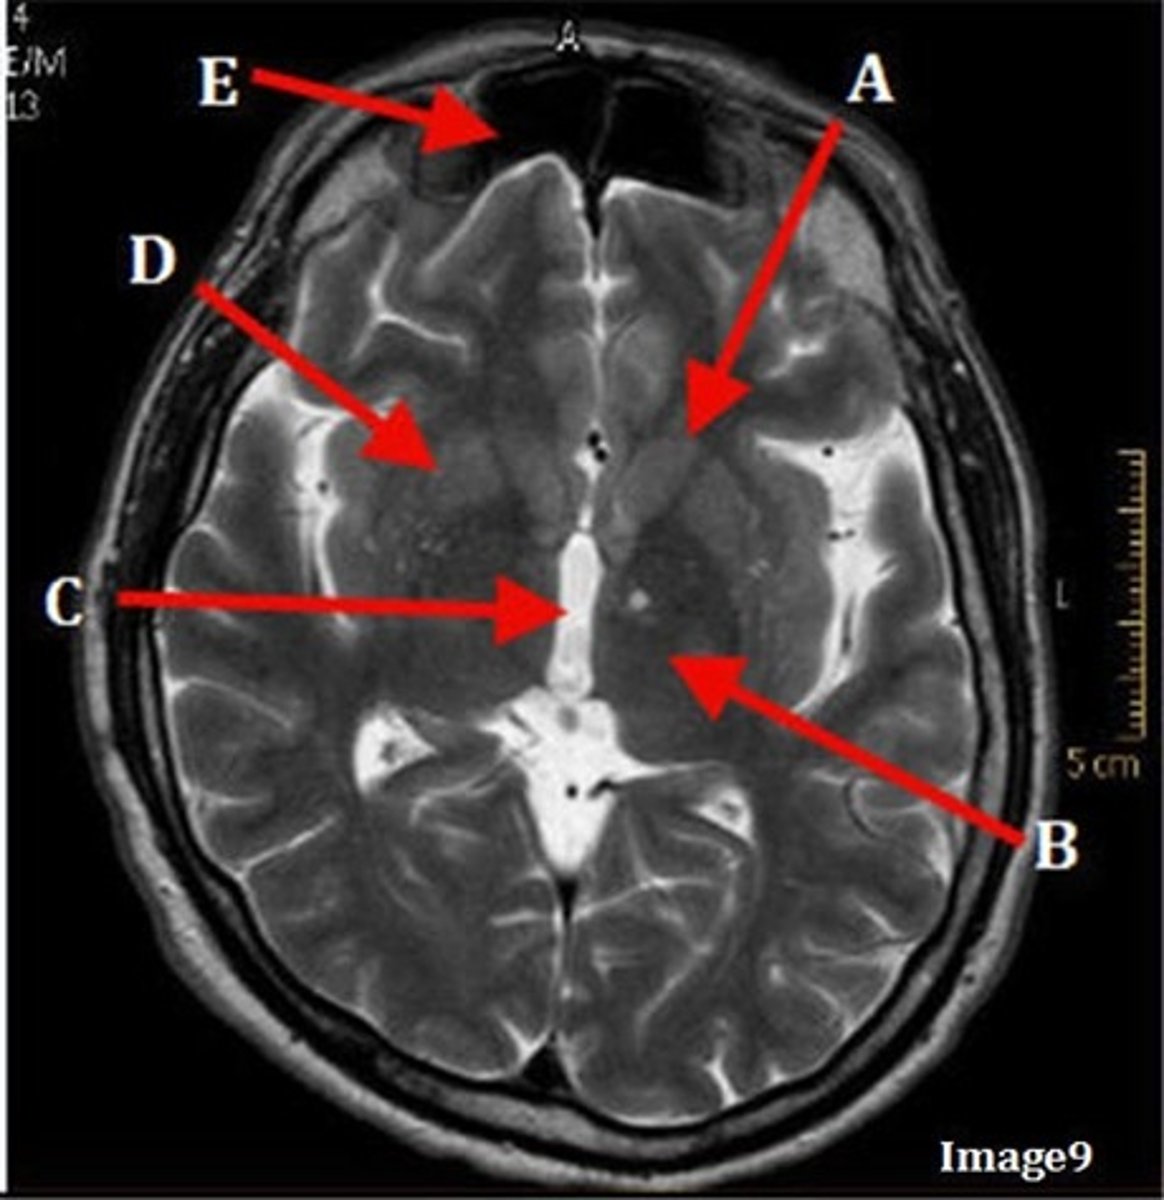

A

caudate nucleus

B

thalamus

C

third ventricle

D

lentiform nucleus

E

frontal sinus